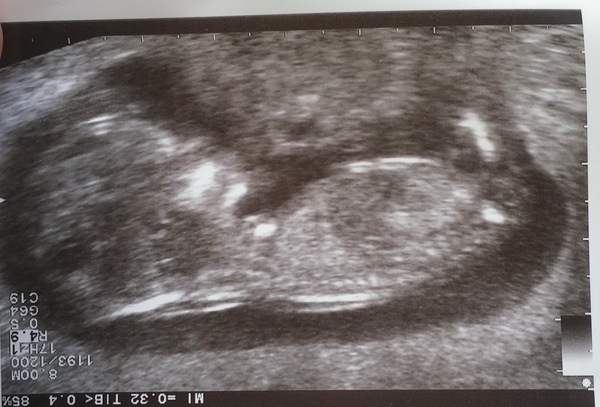

Scan went well. Put me forward a week so due 16th now. So relieved.

Beautiful scan rara. Don't have time to catch up now with all the posts but will have a scroll through this evening.

Rara that's such a lovely scan photo!!